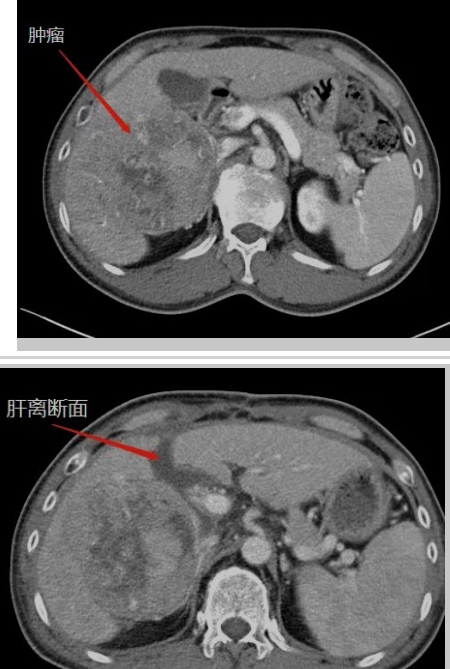

在生命的長(zhǎng)河中,每個(gè)人都在與時(shí)間賽跑,與命運(yùn)抗?fàn)?。而?duì)王晚期肝癌患者來(lái)說(shuō),這場(chǎng)賽跑尤為艱難,這場(chǎng)抗?fàn)幐裢怏@心動(dòng)魄。還記得四年半以前,當(dāng)40多歲的王先生被確診為晚期肝癌伴乙肝、肝硬化時(shí),絕望的陰霾籠罩著整個(gè)家庭。對(duì)王先生來(lái)說(shuō),那是一段黑暗的日子,對(duì)未來(lái)的恐懼,對(duì)生命的不舍,尤其對(duì)年幼的孩子的不舍,讓他...